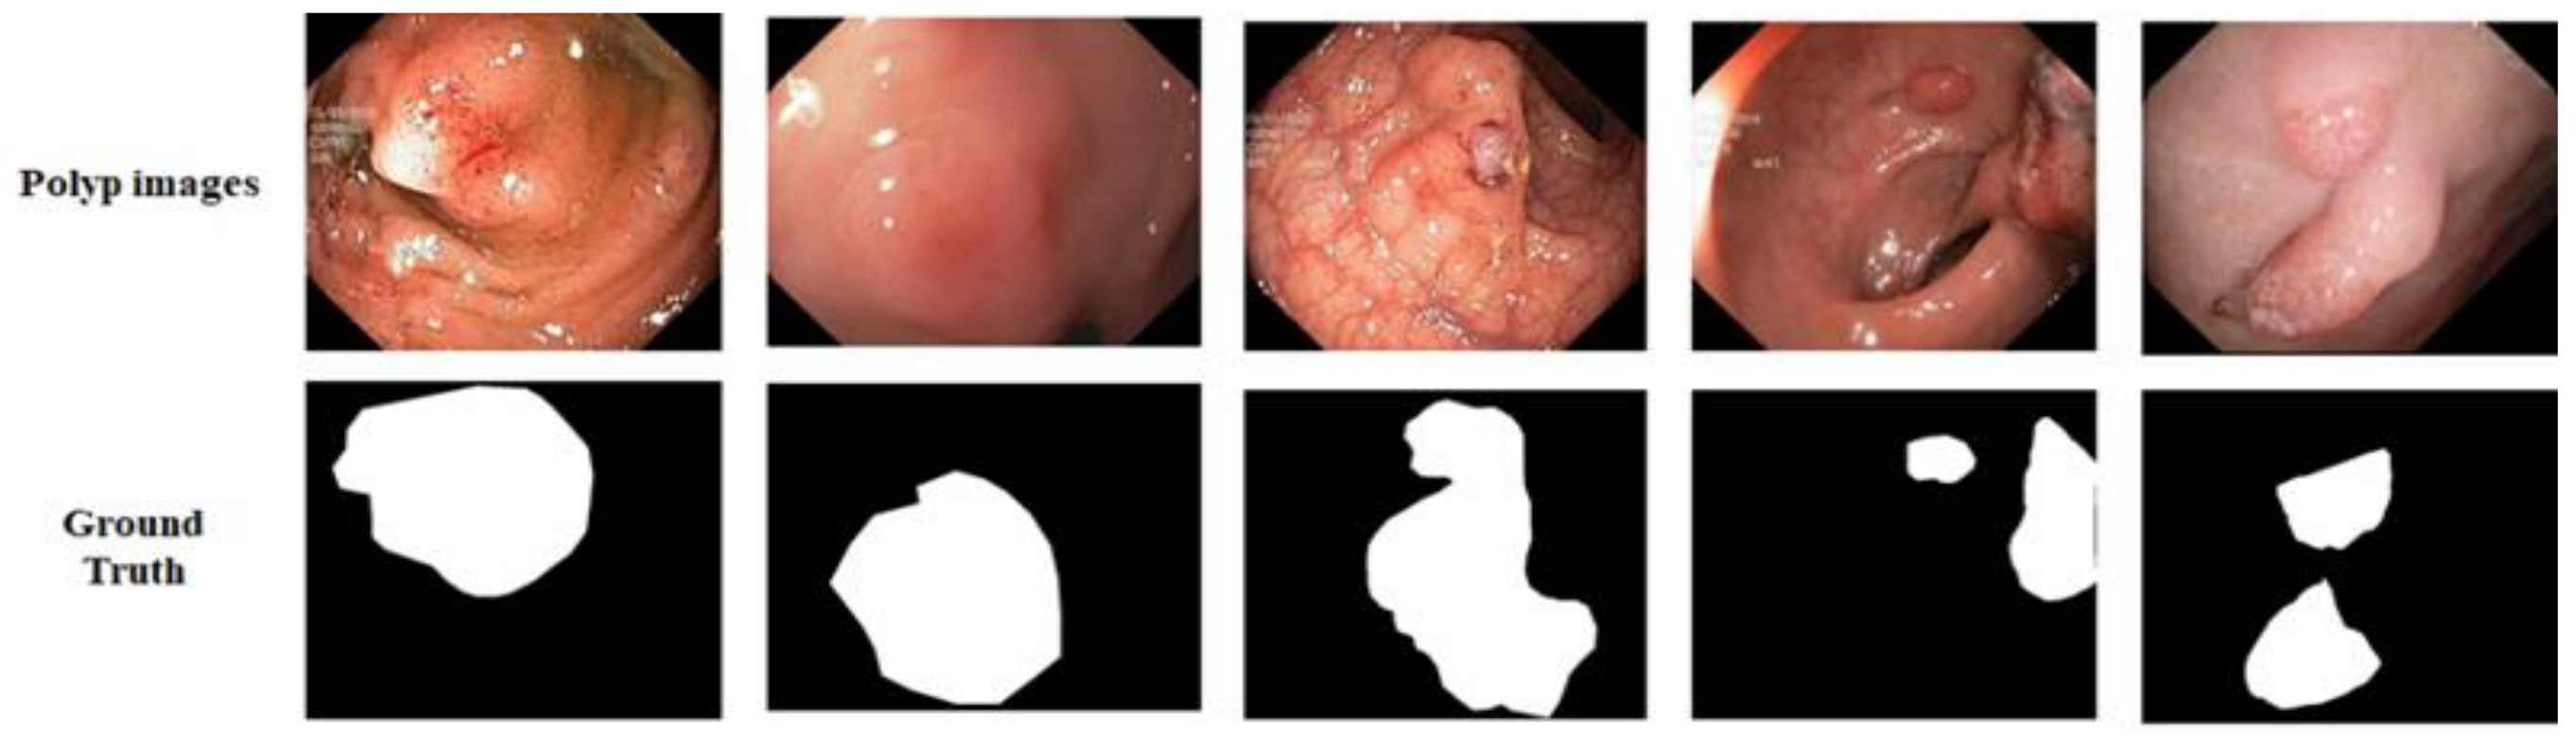

Kvasir-SEG: We utilized the Kvasir-SEG dataset [48], which has 1000 polyp images and their corresponding ground truth masks annotated by professional gastroenterologists from Vestre Viken Health Trust in Norway, as shown in Figure 5. The images have sizes ranging from 332 × 487 to 1920 × 1072 pixels, but training and testing were performed with an image resolution of 224 × 224 pixels. The images were randomly split into 80% for training, 10% for validation, and 10% for testing.

Figure 5.

Example of data from Kvasir-SEG dataset. The first row shows original images and the second row presents their respective ground truth.